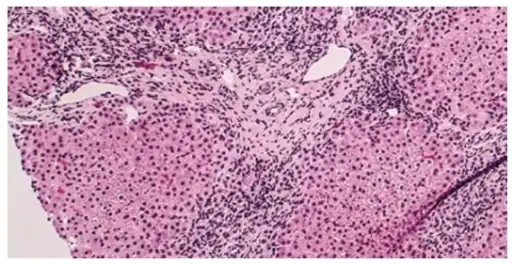

Low magnification micrograph of PBC. H&E stain.

Intermediate magnification micrograph of PBC showing bile duct inflammation and periductal granulomas. Liver biopsy. H&E stain.

On microscopic examination of liver biopsy specimens, PBC is characterized by chronic, non-suppurative inflammation, which surrounds and destroys interlobular and septal bile ducts. These histopathologic findings in primary biliary cholangitis include the following:[34]

- Inflammation of the bile ducts, characterized by intraepithelial lymphocytes, and

- Periductal epithelioid granulomata.

- Proliferation of bile ductules

- Fibrosis (scarring)